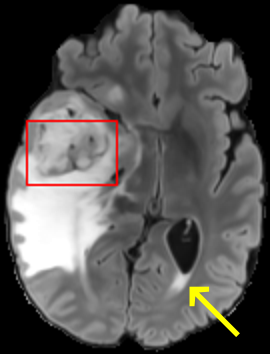

To test the impact of the iterative refinement on YODA’s translation quality, we compared regression and diffusion sampling on the RS data and present additional generation examples in Fig. 6. We observe that diffusion sampling visually resembles the appearance of the acquired images. Regression sampling preserves key anatomical features – the GM/WM boundary, WMHs (Fig. 4), the outline of the pallidum (Fig. 6) – but omits many high-frequency features. To investigate whether iterative refinement during diffusion sampling adds relevant and systematic medical information or only imitates acquisition noise, we performed ExpA sampling, i.e. averaging the output of several ( or ) diffusion trajectories. We observed a gradual loss of high-frequency details when increasing the (see also the supplementary video), indicating that the effect of the iterative refinement is non-systematic. For , the images are visually almost indistinguishable from the initial regression solution (see the supplementary video, and Fig.4 and 6). We directly compared the synthesis results of ExpA () and regression sampling quantitatively and found the differences to be minimal (SSIM: 99.73%, PSNR: 45.30 dB), i.e. diffusion sampling approaches the initial regression solution for a high . The quantitative analysis of the image quality (Tab. 1) showed that diffusion sampling impairs the assessed SSIM and PSNR in comparison to regression sampling for both the in- and external test sets, which we attribute to noise generation (Sec. 3.1). In turn, ExpA averages improved both metrics and, for , performed mostly on par with the regression solution in both test sets in terms of SSIM, while the PSNR in the RS was slightly increased (Tab. 1). However, we observed that ExpA sampling YODA improves the replication of systematic 3D low-frequency image intensity drifts (bias fields) due to the 3D synchronization in 2.5D diffusion sampling. Yet, this apparent advantage did not generalize to the external MBB dataset, as bias fields are MR protocol-specific.

4.1.3 Confirmation in other datasets

For BraTS and IXI datasets, we noted the same convergence of visual appearance for diffusion to regression sampling when increasing the (Fig. 4) as observed in the RS. Also, we observed similar tendencies in terms of SSIM and PSNR, and for the performance of the respective downstream tasks (Tab. 2).

However, we observed some missing small WMHs (third row, Fig. 9) in the synthetic FLAIR images. Due to the weak input signal, translating small WMHs in inherently difficult and, thus, omitting these WMHs can be seen as conservative. In contrast, a more speculative translation bears the risk of false-positive, hallucinated WMHs (compare e.g., SynDiff, Fig. 4).

In Brats, we observed one case with FLAIR hyper- rather than hypo-intense tumor cavity (Fig. 9, fifth row).

While this constitutes a semantic error suggesting soft-tissue rather than fluids, we note that the differentiation from T1w and T2w images alone is ambiguous.